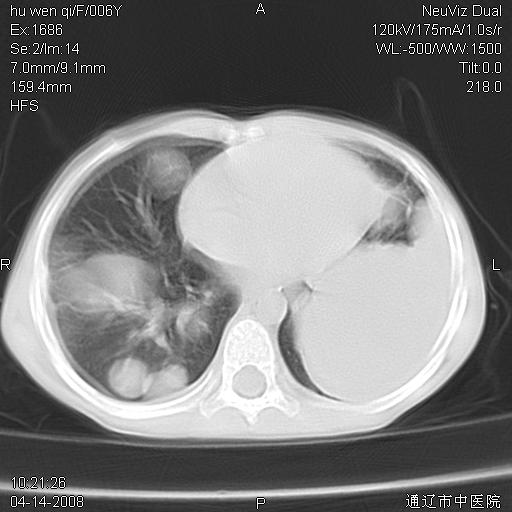

女, 6岁 ,反复咳嗽2周,近两日发热伴右侧胸痛

两肺多发似葡萄状大小不等高密度区,边界清楚,部分见薄壁空洞。左胸壁后方见局限性高密度区,边界清楚,广基与后侧胸壁相连。

考虑:1、金黄色葡萄球肺炎(血源性);

2、左侧包裹性积液;

两肺多发似葡萄状大小不等高密度影,边界清楚,部分见薄壁空洞。左胸壁后方见局限性高密度区,边界清楚,广基与后侧胸壁相连。另示:脾大

2 肺包囊虫病

3、左侧包裹性积液;

两肺多发结节状高密度阴影,边界清楚,部分见薄壁空洞,双侧叶间包裹积液;脾大。可能诊断:1、机遇性感染,肺努卡氏菌病;2、血源性葡萄球肺炎

左肺下叶肿块伴双肺多发大小不一结节。考虑血源性金黄色葡萄球肺炎。

谢谢各位的诊断意见,结果已经出来了,是神经母细胞瘤肺转移,原发病灶在肾,现在已进行放、化疗。